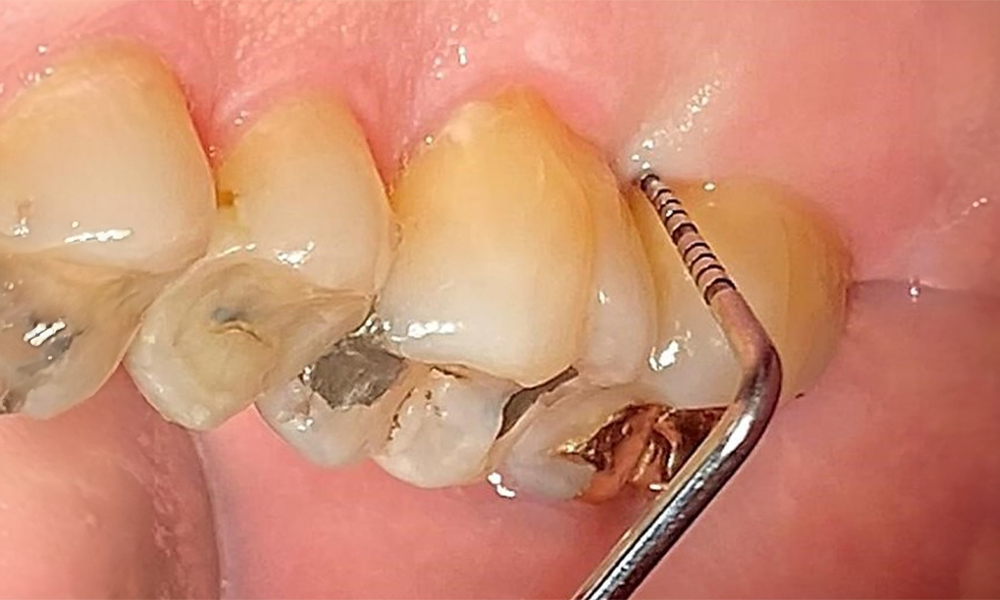

Оклузален изглед на горната челюст. Недостатъчна амалгамена пломба на 14 с маргинална празнина.

Фиг. 5 Оклузален изглед на горната челюст. Недостатъчна амалгамена пломба на 14 с маргинална празнина. © д-р Р. Крапф

Пациентът има пълно съзъбие с 28 зъба, което включва амалгамни и композитни пломби в областта на моларите и премоларите. На зъб 14 има видима клинична маргинална празнина. Зъб 27 има адекватна златна инкрустация. Налице са и генерализирани атриции и абразии. (фиг. 2, фиг. 3, фиг. 4, фиг. 5, фиг. 6)